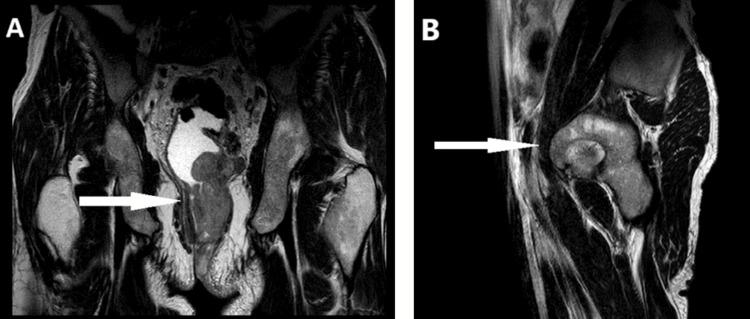

Anorectal mucosal melanoma (AMM) is a rare and highly aggressive malignancy. It frequently presents with nonspecific symptoms, often resulting in delayed diagnosis and poor prognosis. This report describes the case of a 60-year-old male who presented with a painful para-anal papule that progressed to a fistula. Histopathological and immunohistochemical analyses confirmed AMM. Imaging revealed a locally advanced tumor without distant metastasis. Due to the locally advanced nature of the disease, a multidisciplinary team recommended neoadjuvant radiotherapy. This case highlights the diagnostic and therapeutic challenges associated with AMM and emphasizes the importance of a tailored, multidisciplinary approach. Surgical resection remains the cornerstone of treatment, with neoadjuvant therapy potentially improving surgical outcomes in advanced cases.

肛管黏膜黑色素瘤(AMM)是一种罕见且侵袭性很强的恶性肿瘤。它常常表现为非特异性症状,常导致诊断延迟和预后不良。本报告描述了一名60岁男性的病例,该患者最初表现为肛门旁疼痛性丘疹,随后发展为肛瘘。组织病理学和免疫组化分析确诊为AMM。影像学检查显示为局部晚期肿瘤,无远处转移。由于该疾病的局部晚期性质,多学科团队建议进行新辅助放疗。该病例突出了与AMM相关的诊断和治疗挑战,并强调了量身定制的多学科方法的重要性。手术切除仍然是治疗的基石,新辅助治疗可能会改善晚期病例的手术效果。